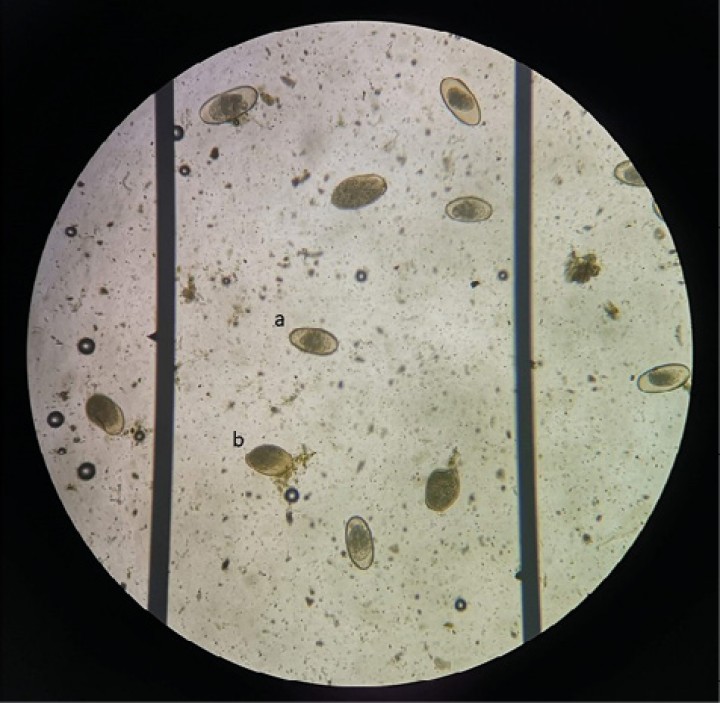

Los huevos encontrados en las coprologías de los quelonios (Fig. 5) pertenecían a la familia Pharyngodonidae, que pertenece al grupo de los oxiúridos de quelonios (suborden Oxyurina). Los recuentos de huevos por gramo de heces (hpg) de los cinco grupos presentaron medias diferentes, pero no existían diferencias significativas (p<0,05) entre ellos en el día 0 del ensayo. Los recuentos de hpg a lo largo del ensayo siguieron un patrón general semejante (Fig. 6 y Tabla 1).

Huevo de oxiúrido (a) y quiste de Nyctotherus (b).